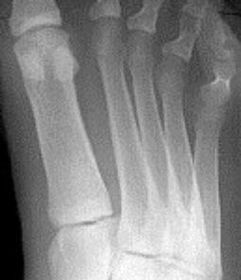

| What type of fracture is shown at the 2nd metatarsal? | Transverse fracture |

| What type of fracture is this? | Oblique fracture |

| What type of fracture is this? | Spiral fracture |

| What type of fracture is this? | Comminuted fracture |